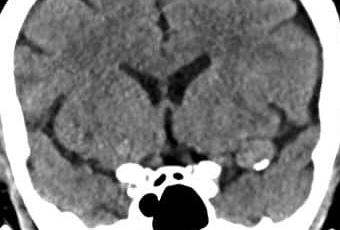

Paciente femenina de mediana edad que acude al servicio de urgencias por presentar convulsiones por primera vez, tras realización de CT de craneo se obtienen las siguientes imagenes:

La lesion evidenciable se encuentra:

a) extraxial

b) intraxial

Probable estirpe etiologica de la lesion:

a) glial

b) dural

c) vascular

d) ependimaria

Las areas hiperdensas sugieren?:

a) sangrado activo

b) sangrado antiguo

c) calcificaciones vasculares

d) fragmentos oseos